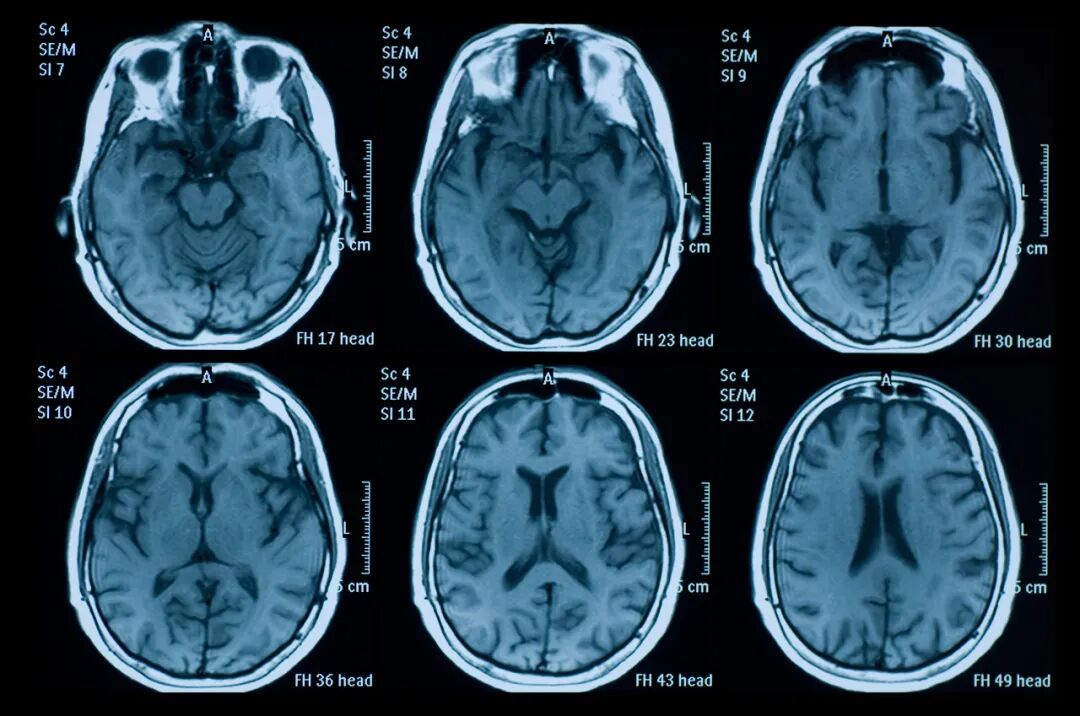

2017年,在一项间充质干细胞治疗10例急性脑卒患者,治疗3月后,所以患者NIHSS评分和BI指数都有不同程度改善。在治疗前,7患者上肢无力并且有严重的言语障碍,现在所有患者的手已经可以自由控制了,核磁共振结果显示,所以患者的脑组织并没有进一步受损,改善脑卒中患者的神经功能恢复的作用。干细胞可以通过抑制炎症反应、调节免疫应答、分化为成熟神经元或内皮细胞、促进神经突触重塑、促进神经再生和血管再生、分泌神经营养因子等多种途径发挥治疗中风的作用。